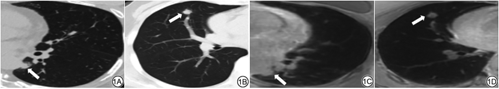

肺结节位置对UTE MRI检出肺结节的能力存在影响,HUANG等 [15]研究提示,由于心脏和呼吸运动伪影的存在,位于左肺下叶和右肺中叶的肺结节在UTE MRI中的检出率较其他部位有一定程度地降低,而且周围型肺结节比中心型肺结节的检出率高。当肺结节位于肺下叶后基底段时,由于呼吸运动在肺底部产生的坠积效应影响,结节往往显示不清,容易漏诊[2]。此外,也有研究显示结节检测率与胸膜距离相关,胸膜下(与胸膜距离<5 mm)结节的检出率为66%,非胸膜下(与胸膜距离≥5 mm)结节的检出率为79%[18]。图1展现了不同部位肺结节在CT和UTE MRI图像中的表现。